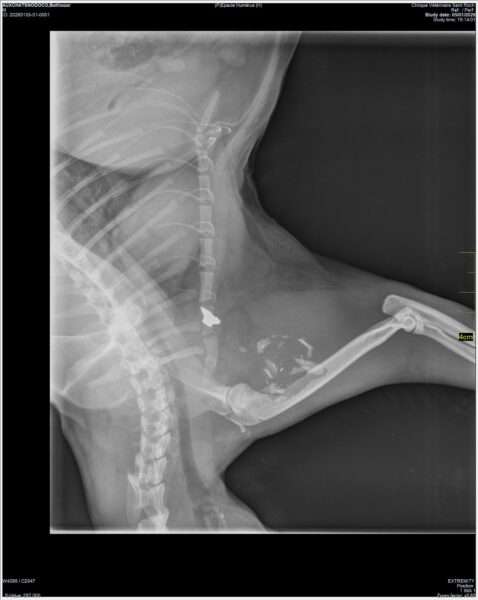

Radio Balthazar

👉 Balthazar a été touché par balle.

Une balle logée dans l’épaule